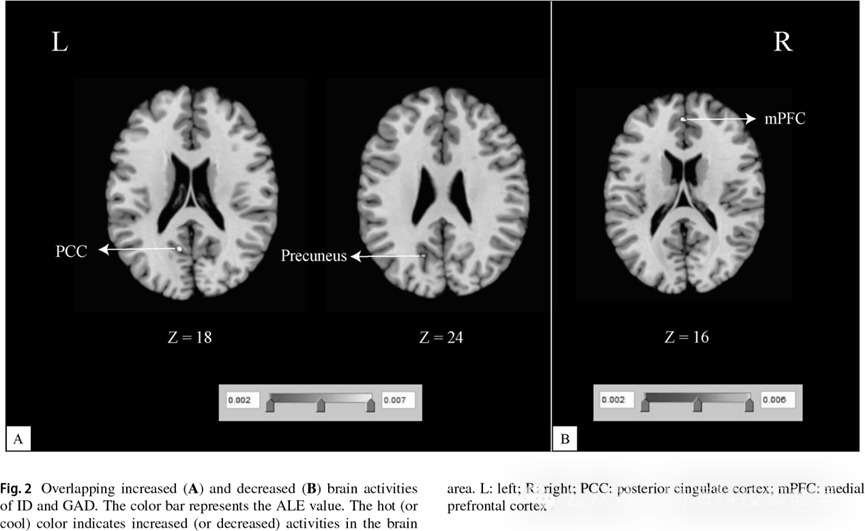

二级分析结果;重叠的脑活动增强区域(图 2A);重叠的脑活动降低区域(图 2B

ID > HC  GAD > HC 的联合分析结果显示,左侧后扣带回(posterior cingulate cortexPCC)和左侧楔前叶(precuneus)为两种障碍中共同表现出脑活动增强的脑区(见表 3、图 2A)。ID < HC  GAD < HC 的联合分析结果表明,两种障碍中共同表现出脑活动降低的脑区位于左侧内侧前额叶皮层(medial prefrontal cortexmPFC(见表 3、图 2B)。

在本研究中,采用基于坐标的激活似然性评估(ALE)元分析方法,探讨了IDGAD之间脑功能活动的共性与差异性模式。综合元分析结果显示,IDGAD左侧后扣带回(posterior cingulate cortexPCC)和左侧楔前叶(precuneus)表现出一致的脑活动增强,同时在左侧内侧前额叶皮层(medial prefrontal cortexmPFC)表现出一致的脑活动降低。此外,与 ID 患者相比,GAD 患者在左侧额上回(superior frontal gyrusSFG)表现出更显著的脑活动增强。进一步的 Jackknife分析表明,上述结果具有良好的稳定性与可重复性本研究结果提示,IDGAD均存在复杂的静息态脑功能异常,并为理解两种障碍在神经病理生理机制上的共性与特异性特征提供了更为可靠的神经影像学证据

本研究的元分析结果显示,左侧后扣带回(posterior cingulate cortexPCC)和左侧楔前叶(precuneus)存在一致性的脑活动增强模式PCC是与自我相关加工、内感受以及情绪调节密切相关的关键脑区。既往研究表明,PCC 参与了ID的发病过程,且在ID患者的各个睡眠阶段中均表现出 PCC活动增强。此外,PCC注意分配与信息理解中亦发挥重要作用。静息态下 PCC的过度激活提示情绪整合过程异常,可能导致ID与广泛性焦虑障碍患者出现难以控制的焦虑情绪。楔前叶不仅参与视觉加工,还与情境记忆及复杂认知功能密切相关。既往研究已报道ID患者楔前叶活动显著增强,同时该脑区的功能活动也被证实与焦虑情绪水平相关。因此,推测PCC与楔前叶的功能异常可能对IDGAD患者的失眠与焦虑症状产生不利影响

除上述过度激活脑区外,本研究还发现IDGAD患者在左内侧前额叶皮层(medial prefrontal cortexmPFC)存在一致性的脑活动降低。作为默认模式网络(default mode networkDMN)的关键节点mPFC信息接收、整合与传递过程中起着核心作用,并广泛参与情绪调控、决策、注意及警觉性维持。大量研究表明,mPFC参与REM睡眠的调节,且ID患者在该脑区表现出异常的功能活动。在GAD患者中,焦虑严重程度及内感受敏感性亦与mPFC的功能活动密切相关。本研究的元分析结果显示mPFC呈现去激活状态,可能反映了IDGAD患者在内感受、信息加工及情绪表达方面的内在神经机制异常。总体而言,本研究发现IDGAD患者的功能异常主要集中于默认模式网络相关脑区,提示DMN的异常活动可能是两种障碍共享的神经生物学基础,从而解释其在情绪调节、认知功能及记忆功能方面的受损表现。此外,控制分析结果显示主要发现具有良好的稳定性,进一步表明本项元分析结果具有较高的可靠性

本研究识别出IDGAD在默认模式网络相关脑区中的一致性功能活动改变,主要涉及左侧后扣带回(posterior cingulate cortexPCC)、左侧楔前叶(precuneus)及左侧内侧前额叶皮层(medial prefrontal cortexmPFC,提示上述脑区可能构成ID GAD共同神经通路。此外,本研究还发现IDGAD 在左侧额上回(superior frontal gyrusSFG)存在差异性激活模式,表明两种障碍可能具有特异性的神经机制。这些发现为未来临床干预与治疗策略的制定提供了潜在的参考依据。